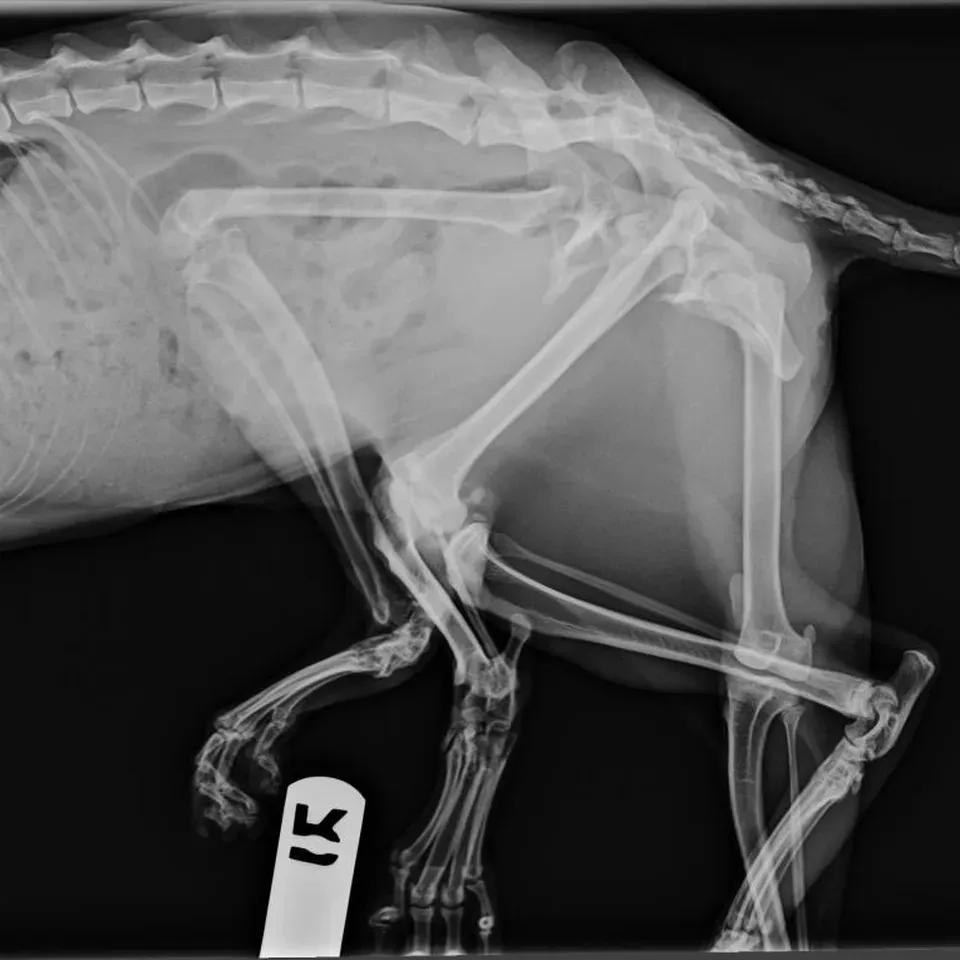

Bitsy valószínűleg beolvasztotta a testvérét saját növekvő testébe az anyaméhben. A cica két medencecsonttal és hat lábbal élte az életét, amíg a segítségére nem siettek. Az extra testrészek fájdalmat okoztak az állatnak és nehezítették őt a mozgásban. Az extra lábait nem tudta használni, azok fordítva csatlakoztak a testéhez, amely megnehezítette azt, hogy a másik két hátsó lábát jól használja. A megfigyelés következtében kiderült, a cica hat lábából csak hármat tudott használni.

A műtét során a macska három lábát eltávolították a testről, hogy véget vessenek az állat fájdalmának és mozgási nehézségeinek. Az állat viselkedése a műtét után nagy változásokon ment át. Végre nyugodtan le tudott feküdni az extra végtagok nélkül, és könnyebben tudott járni. Bitsy-t az egyik állatorvosi munkatárs fogadta örökbe, aki segített neki a műtét utáni felépülésben - írja a Mirror.